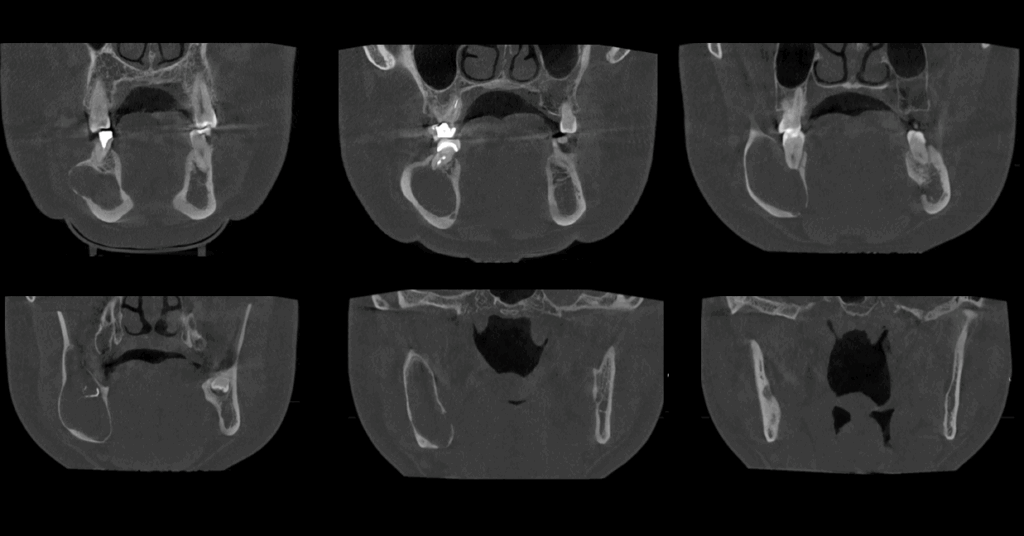

A la evaluación de la tomografía volumétrica (cone beam) bimaxilar en los cortes axiales (Figura 2), coronales, (Figura 3) y tangenciales (Figura 4) se observa imagen isodensa irregular, ubicado en cuerpo, ángulo y rama ascendente mandibular de lado derecho, que se extiende desde zona periapical mesial de pieza 44, hasta tercio medio de rama mandibular, y desde tercio superior (próximo a base de apófisis coronoides) hasta basal mandibular ocasionando expansión de tablas ósea, adelgazamiento de corticales y pérdida de continuidad de tabla vestibular en zona de pieza 45 y de tabla ósea lingual a en zona de pieza 46, 48 y rama mandibular. Además de producir el desplazamiento caudal y borramiento parcial de las corticales del canal mandibular; así mismo, se observó reacción periostal en tabla ósea vestibular (próxima a escotadura sigmoidea), ángulo mandibular y en basal mandibular de zona antegonial. Se pudo evidenciar tambien a la pieza 48 incluida y con reabsorción severa 48 dejando solo restos de esmalte.

CORTES AXIALES

CORTES CORONALES